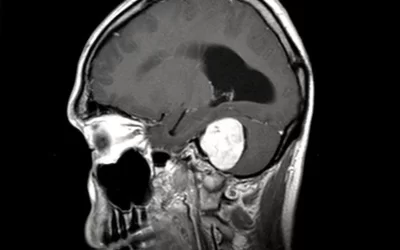

تومور عصبی شنوایی (نوروم آکوستیک)

آیا تا به حال احساس کردهاید که صدایی دائمی در گوشتان میپیچد یا شنواییتان کم شده و علت مشخصی برای آن پیدا نمیکنید؟ این...

تومورغده هیپوفیز خطرناک است؟

تومور هیپوفیز یک نوع تومور است که در غده هیپوفیز واقع در قاعده مغز ایجاد میشود. این غده مسئول تولید و تنظیم هورمونهای...

تومورهای قاعده جمجمه را بیشتر بشناسید

تومورهای قاعده جمجمه نوعی از تومورها هستند که در بخش پایینی جمجمه، تشکل میشوند. این تومورها ممکن است از بافتهای مختلفی...